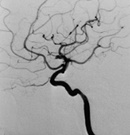

Both right-sided paralysis and loss of expressive speech are clear symptoms of a stroke of the left middle cerebral artery, where the blood flow is blocked – leading to the death of the surrounding brain tissue, suggesting that the Psalm may be wishing these effects on people who forget the importance of Jerusalem.